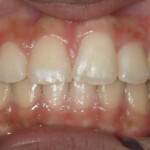

Before Transformation!